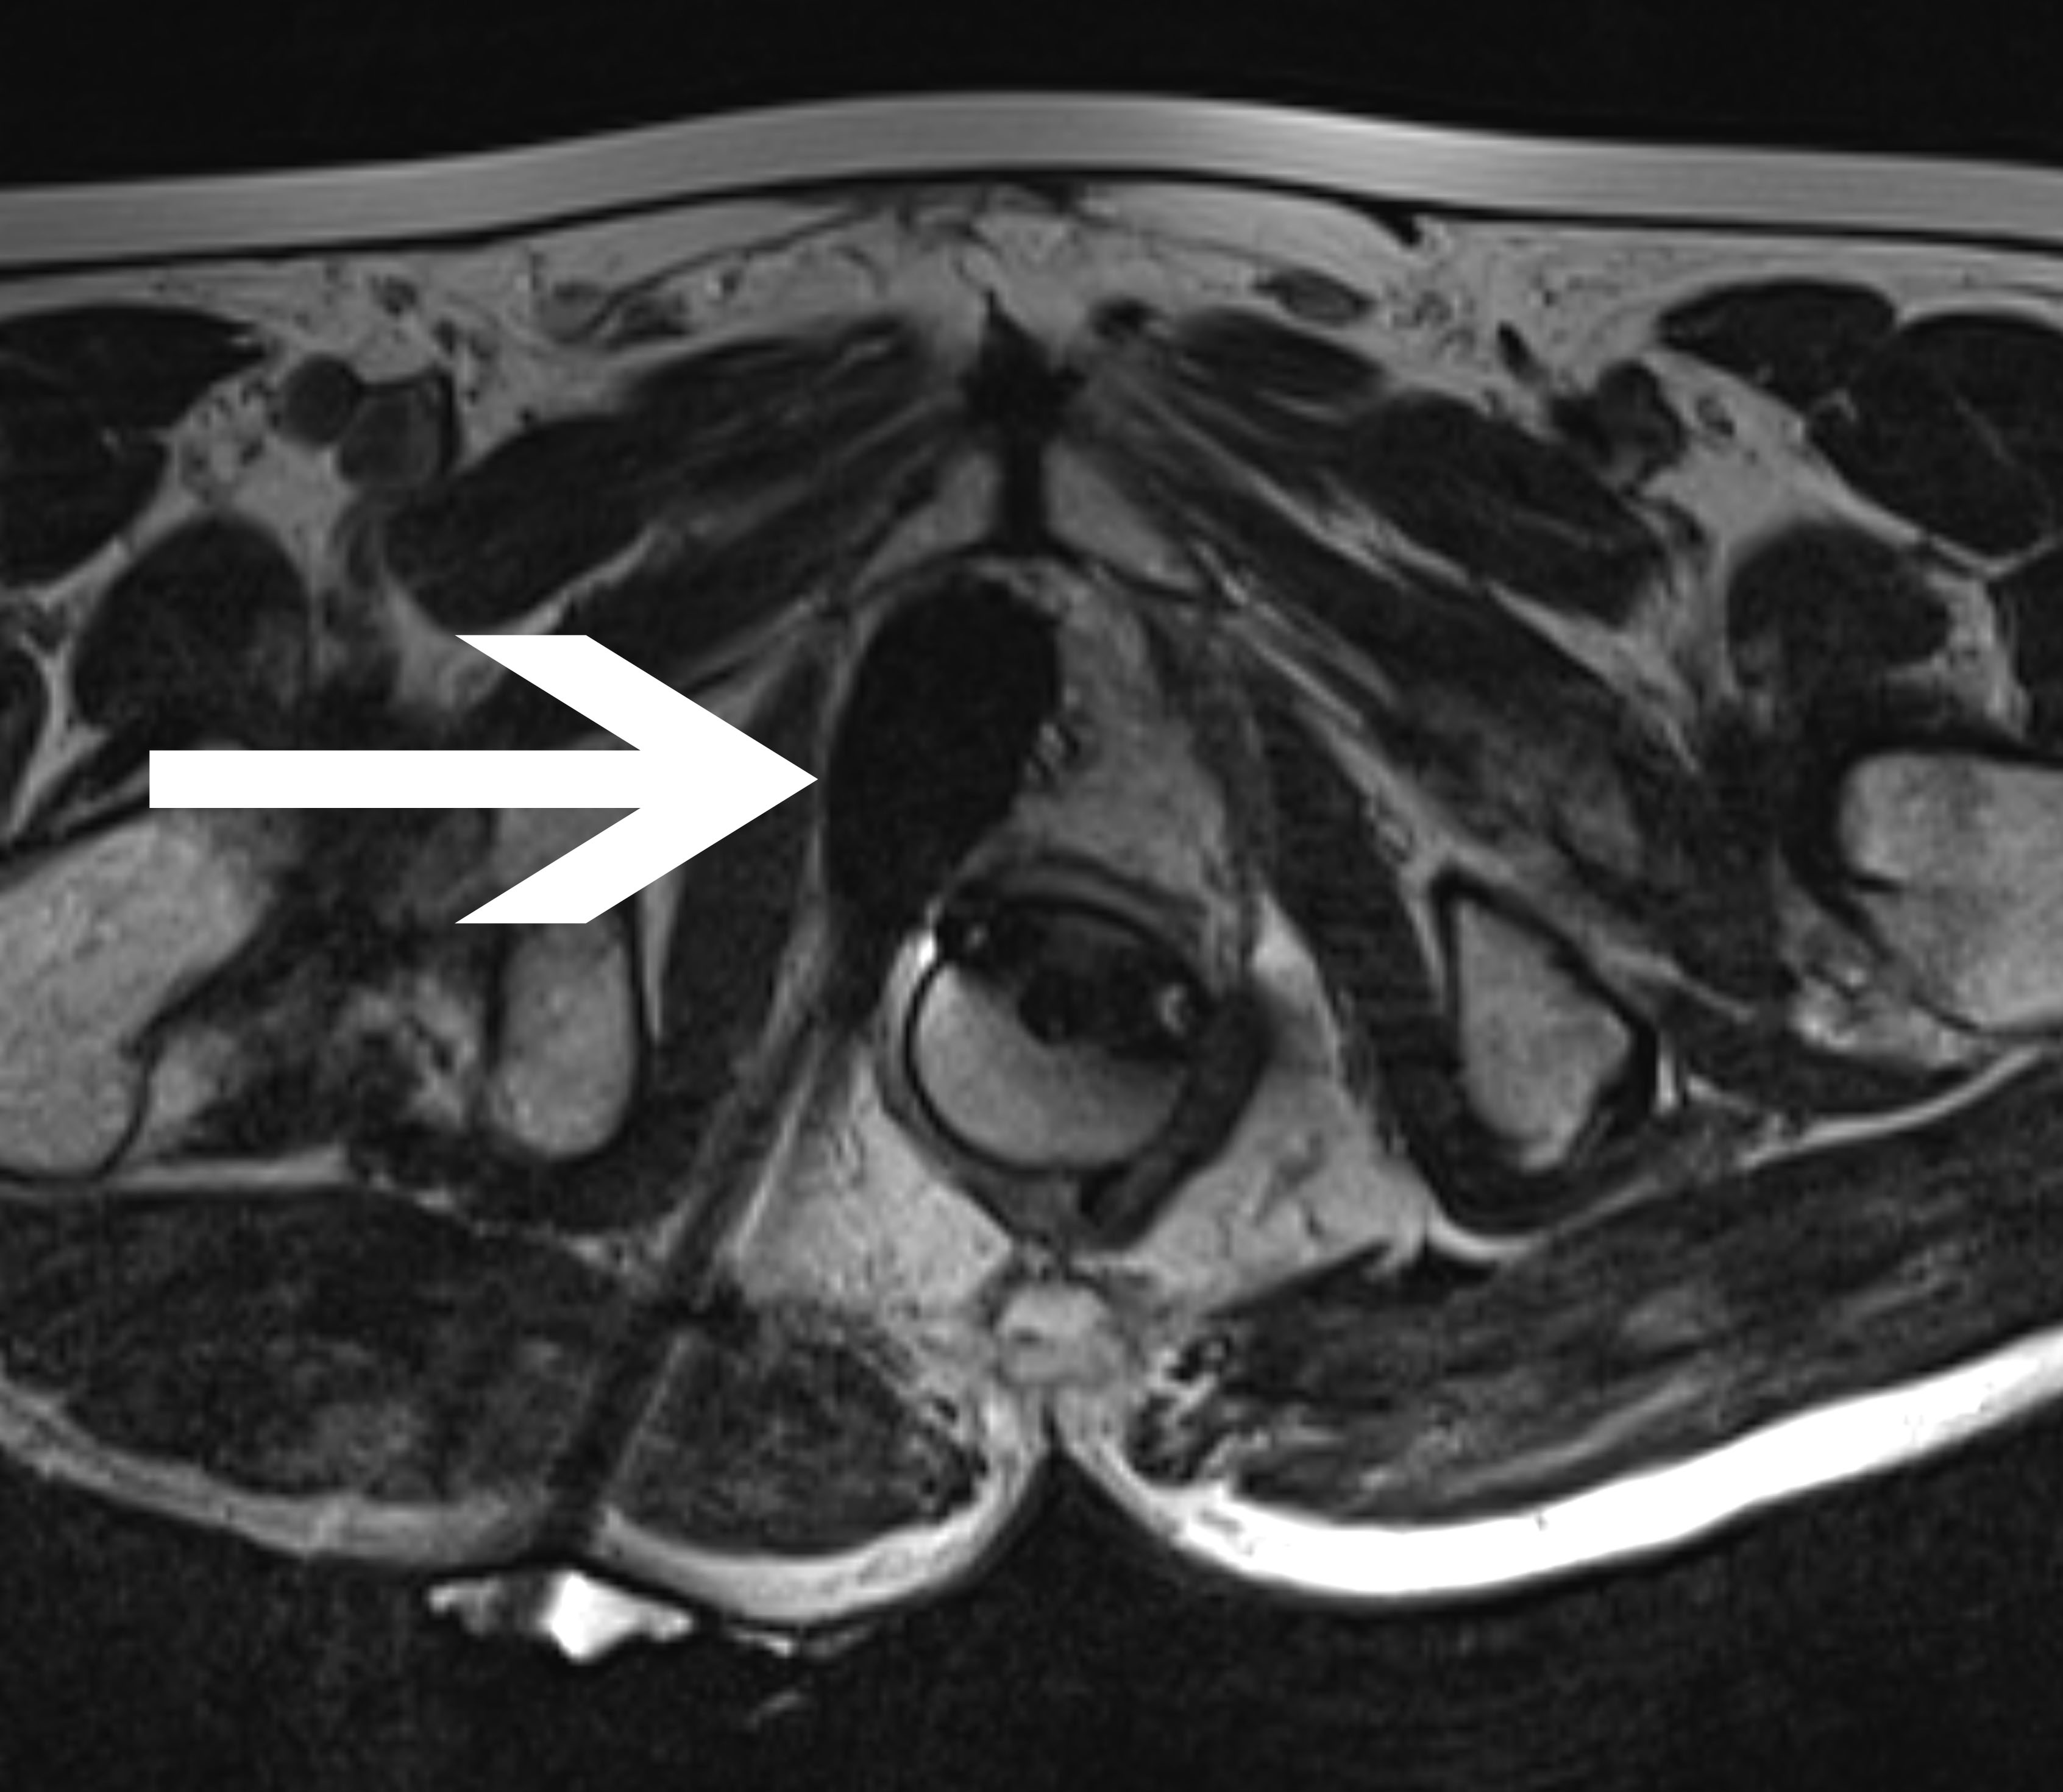

Abb 2:

Periinterventionelles MRT mit

transgluteal positionierten

Kryoablationssonden und dem

anhand des schwarzen

Auslöschungsartefakts erkennbaren

Ablationsareal innerhalb der

Prostata in:

- koronarer Ansicht

- transversaler Ansicht

- sagittaler Ansicht